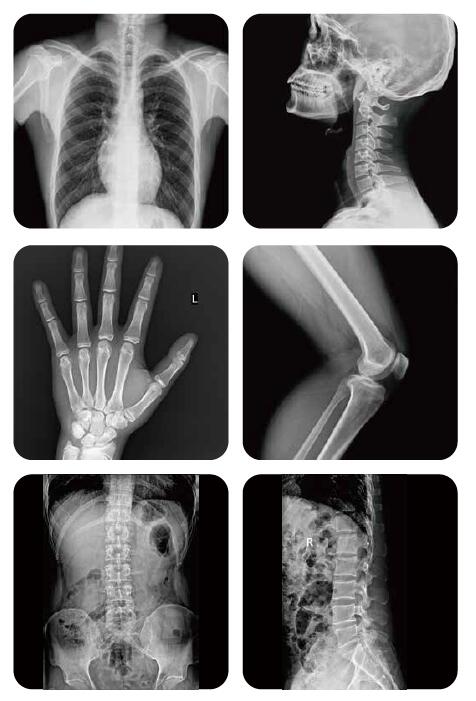

Registered exposure programs

The system can register up to hundreds of exposure parameters regard to different anatomies and positions, making it always easy for radiography examination.

Fast imaging

The system can automatically process the acquired image, bring clear image with speed and improving examination efficiency.

Image post-process

Performing post-processing immediately after acquiring each image based on preset image database,ensuring the best image quality.